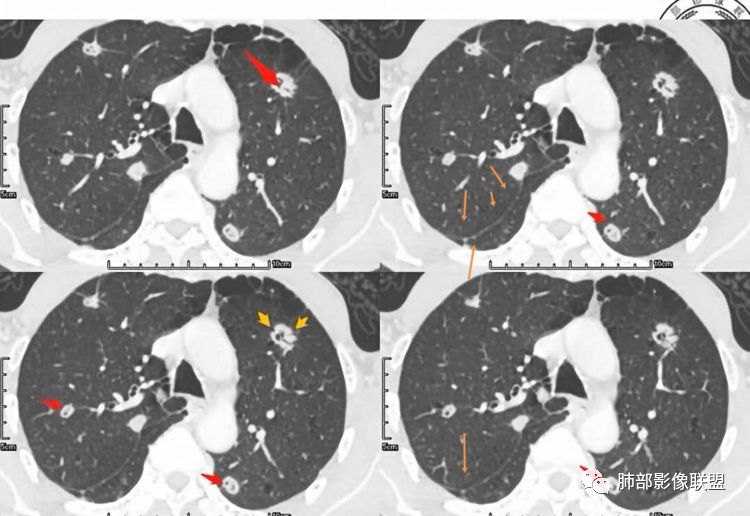

张延军:双肺多发结节,空洞影,后者洞壁厚薄不均匀,部分腔内丝丝落落,呈分叶征,边缘见毛刺影,病灶大部分位于胸膜下,与血管相连,右肺下叶前基底段结节近段支气管截断,远端见空腔。左肺下叶病灶密度不均,背段支气管壁增厚,管腔狭窄。考虑1.双肺下叶占位性病变伴肺内空洞性转移 2.多原发的占位 3.肉芽肿性血管炎代排。

大家按我提的单个病灶分析,很多提出来都是典型的腺癌

脐凹征、粗短毛刺、深分叶、中央结构杂乱

本病例左肺下叶肿块,有深分叶、毛刺、胸膜牵拉凹陷、支气管截断及纵隔内淋巴结肿大等征象,都均支持病灶为恶性,如腺癌,而且叶间裂的多发结节也提示是腺癌来源可能大;双肺多发结节、肿块,大部分病灶有分叶、毛刺及胸膜凹陷的恶性征象,与原发肿瘤本身的性质有关,所以应该与左肺下叶肿块同源,而且双肺多发病灶内空洞也具有多样性;

此病例中空洞形态多样,内壁不光整,有分隔影,周围未见明显卫星灶及钙化灶,结核不太符合;患者病史慢性病史,无明显发热,缺乏中毒临床表现,急性感染基本排除;各种中性粒细胞胞浆抗体阴性,没有鼻窦炎,肾脏等病史,基本排除血管炎;霉菌性空洞常见于免疫机能低下者, 常为空洞、肺炎、伴“ 晕圈”征的结节及支气管扩张合并存在。